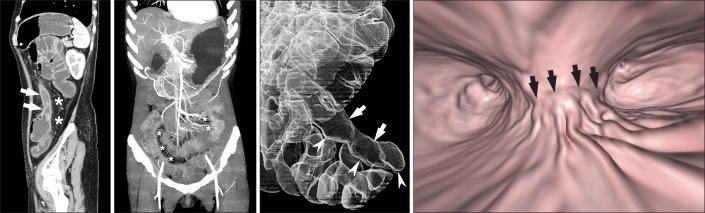

Imaging of the small bowel is complicated by its length and its overlapping loops. Recently, however, the development of crosssectional imaging techniques, such as computed tomography enterography (CTE) and magnetic resonance enterography (MRE) has shifted fundamental paradigms in the diagnosis and management of patients with suspected or known Crohn's disease (CD). CTE and MRE are noninvasive imaging tests that involve the use of intraluminal oral and intravenous contrast agents to evaluate the small bowel. Here, we review recent advances in each cross-sectional imaging modality, their advantages and disadvantages, and their diagnostic performances in the evaluation of small bowel lesions in CD.